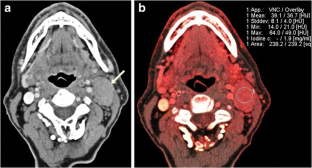

To evaluate whether dual-energy computed tomography (DECT)-derived iodine content and iodine overlay could differentiate between normal, inflammatory and metastatic squamous cell carcinoma (SCC) cervical lymph nodes.

This study was approved by the institutional review board. Sixteen patients with normal lymph nodes, 20 patients with enlarged nodes draining deep cervical inflammations and 23 patients with pathologically proved metastatic SCC nodes who underwent contrast enhanced DECT were retrospectively identified. Iodine content and overlay of 36 normal, 43 inflammatory and 52 metastatic lymph nodes were calculated using circular regions of interest and compared among the three groups. A receiver operating characteristic (ROC) curve was used to determine the sensitivity and specificity of iodine content and overlay for diagnosis of metastatic nodes.

Iodine content (mg/ml) was significantly lower for metastatic lymph nodes (2.34 ± 0.45) than for normal (2.86 ± 0.37) and inflammatory (3.53 ± 0.56) lymph nodes, P < 0.0001. Iodine overlay (HU) was also significantly lower for metastatic lymph nodes (47 ± 11.6) than normal (57.4 ± 8.2) and inflammatory nodes (69.3 ± 11.5), P < 0.0001. The areas under the ROC curve for iodine content and iodine overlay were 0.923 and 0.896.

DECT-derived iodine content and overlay differ significantly among normal, inflammatory and metastatic SCC cervical lymph nodes.